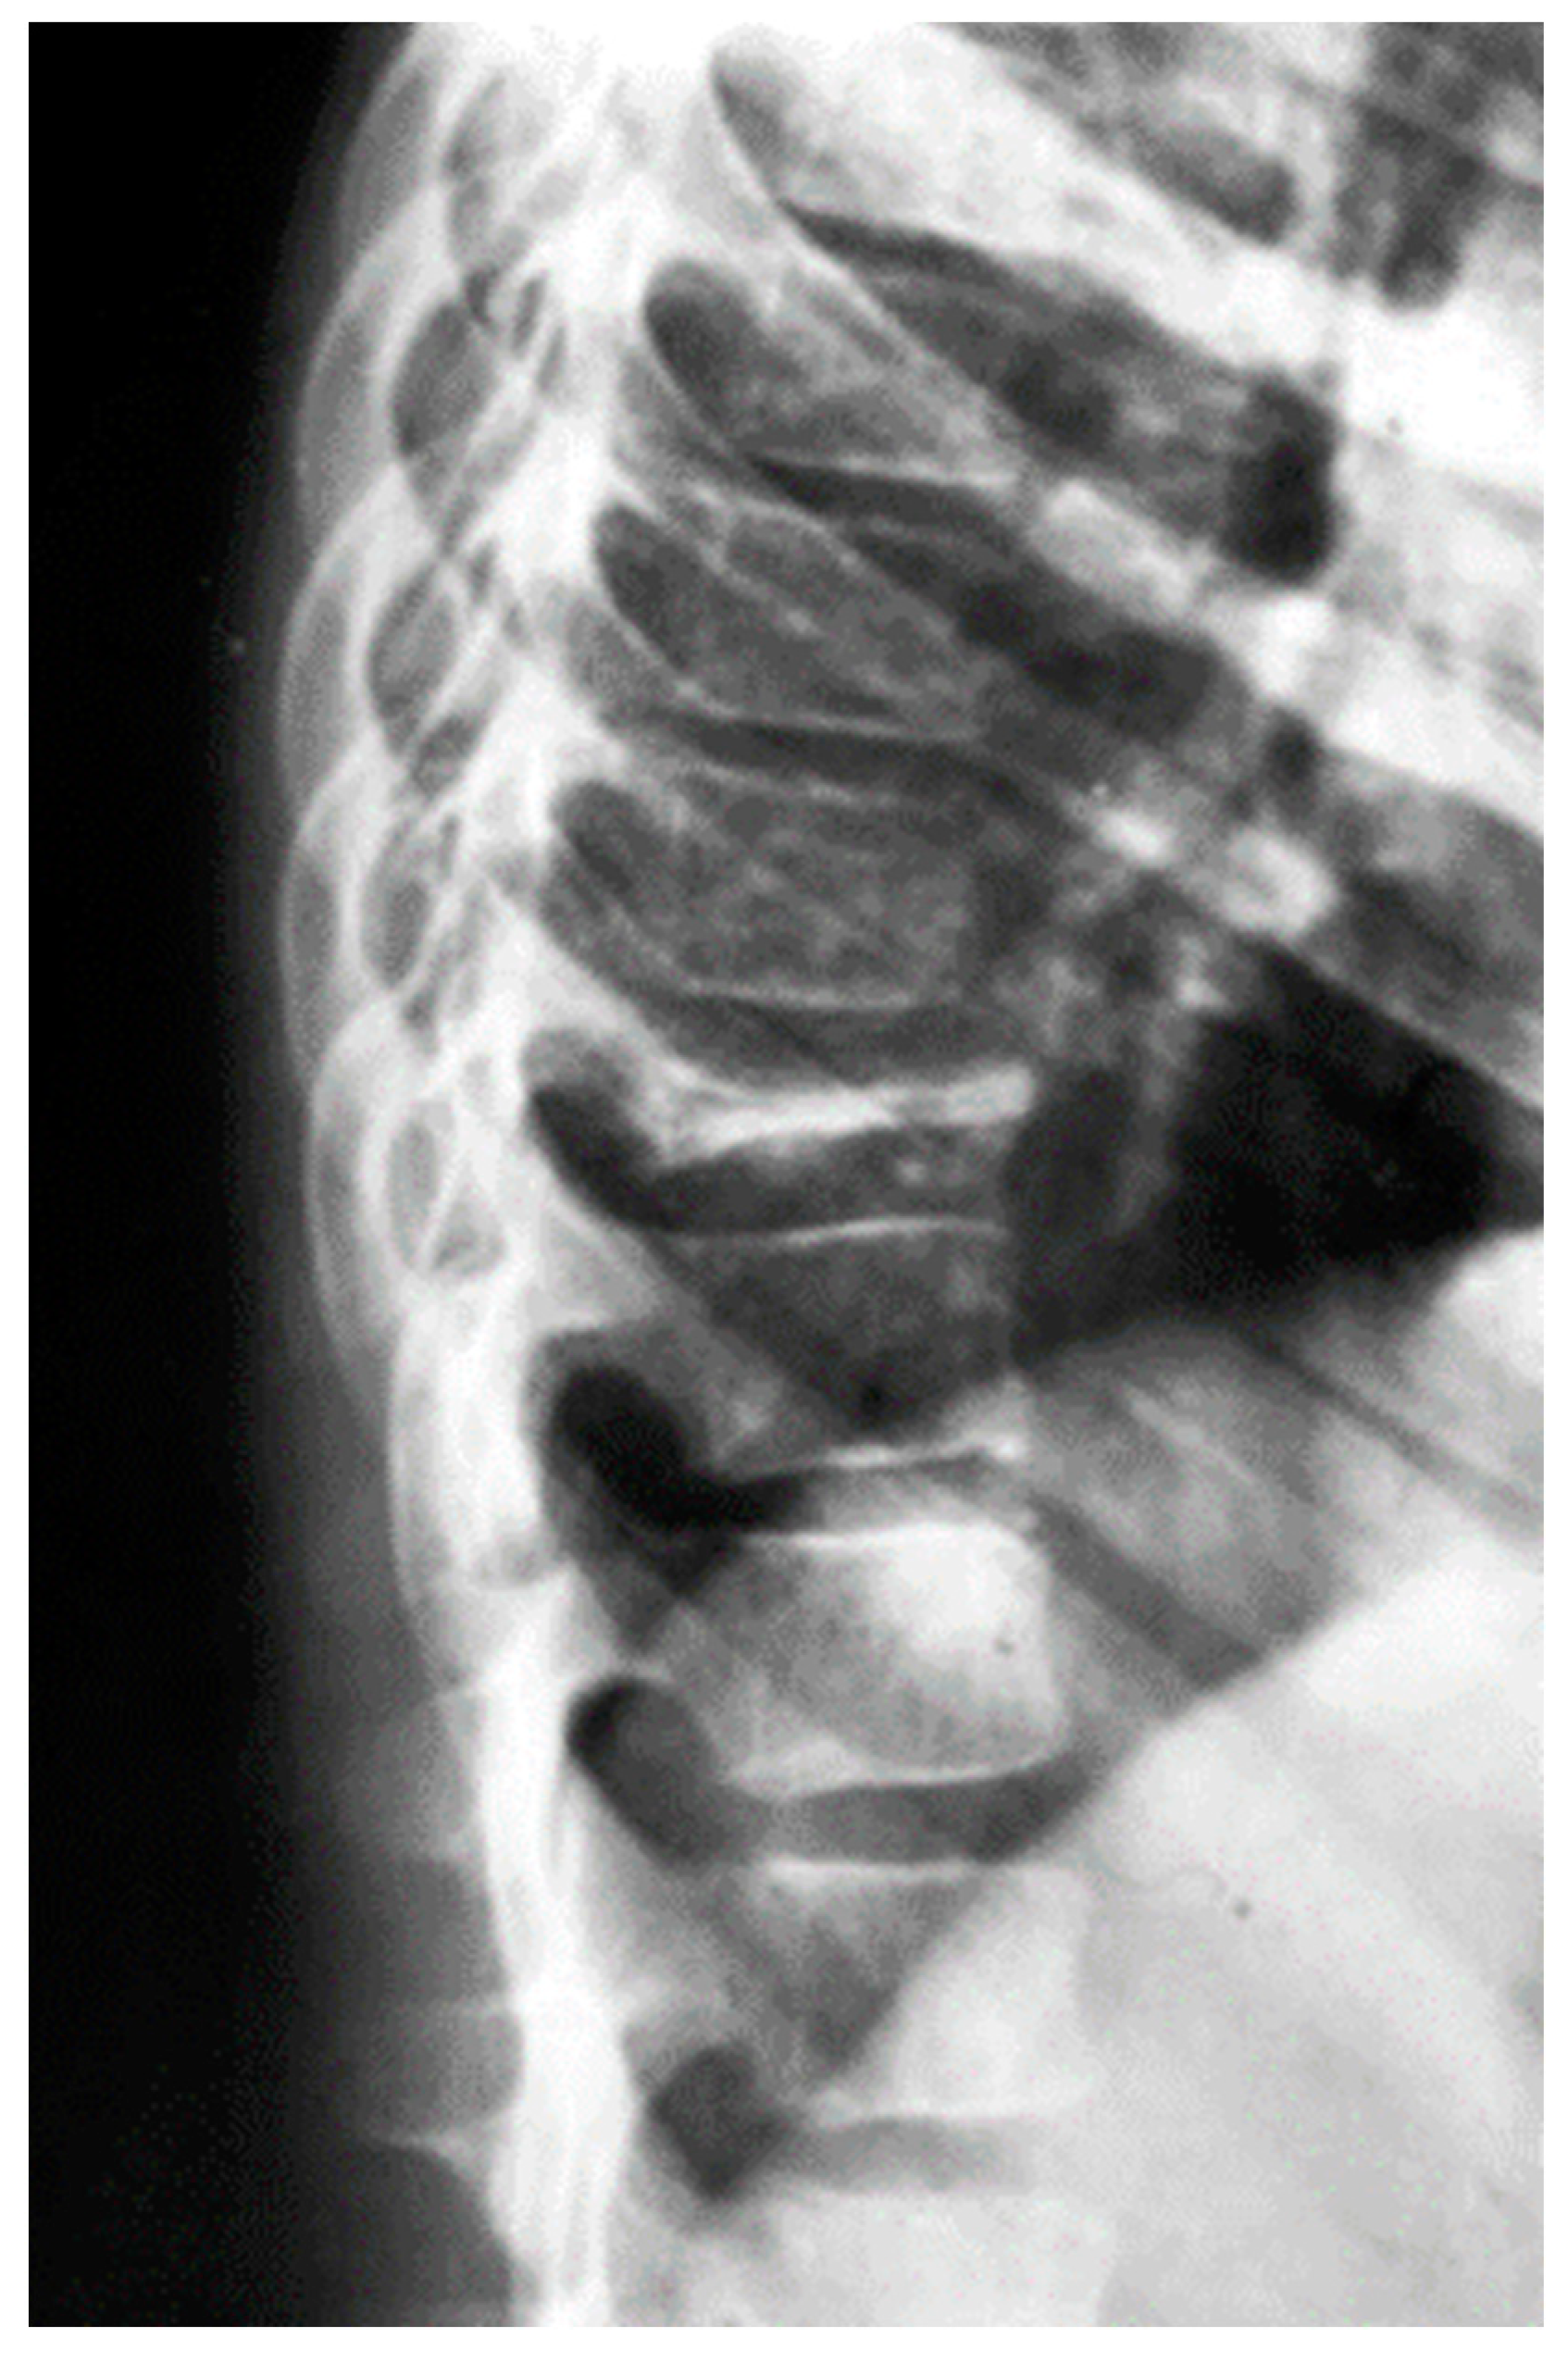

Langerhans Cell Histiocytosis